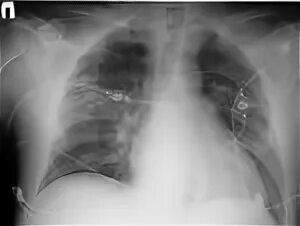

Атеросклероз легких